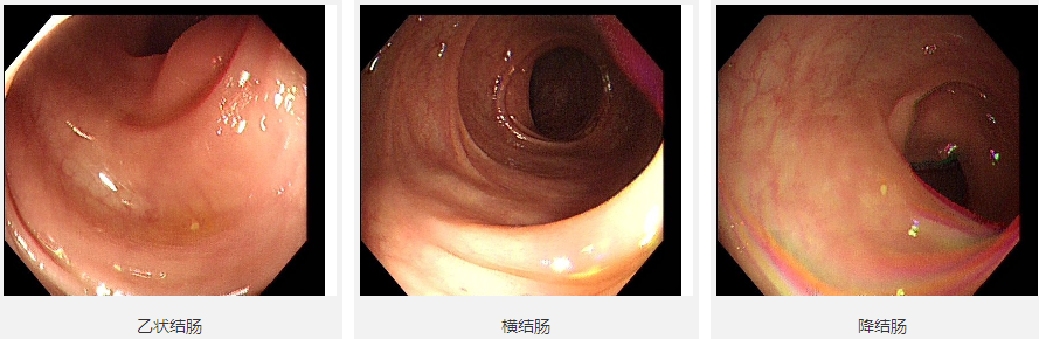

2016-04-19肠镜

【内镜所见】入镜7cm见直肠菜花样肿物,环腔狭窄,不能再入镜,予多点活检。

【内镜诊断】直肠中下段Ca.

肠镜病理:直肠腺癌

2018-12-12肠镜